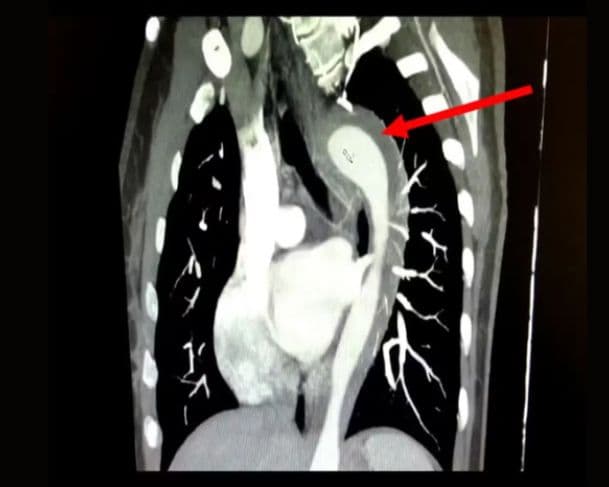

Ao chegar ao hospital, exames revelaram um hematoma intramural, um tipo de sangramento interno na parede da aorta, característico da chamada Síndrome Aórtica Aguda (SAA), uma condição potencialmente fatal que pode evoluir para ruptura total da artéria e levar à morte em poucas horas se não for tratada.